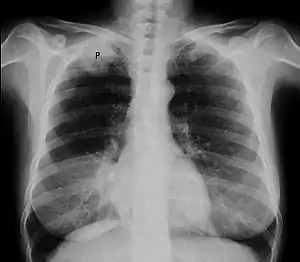

![]() | |

| Chest X-ray showing a Pancoast tumor (labeled as P, non-small cell lung carcinoma, right lung), from a 47-year-old female smoker. | |